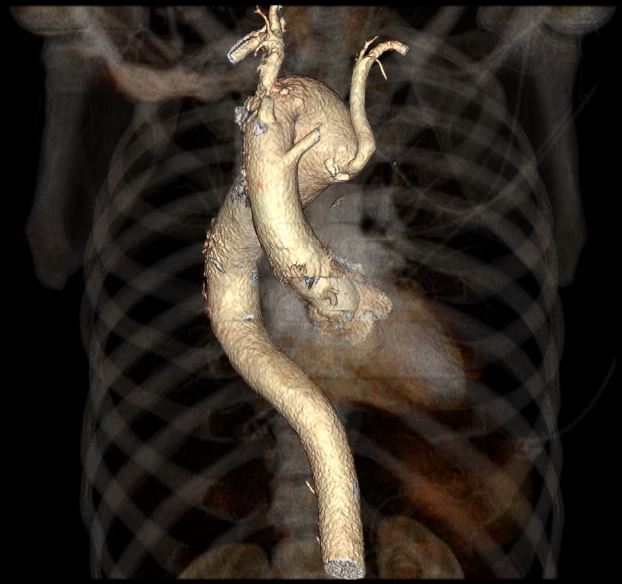

Case Presentation: 56-year-old male patient with PMHx of HTN, HLD, pulmonary embolism and cigarette smoking presented to the emergency department with recurrent chest pain. He described his chest pain as substernal, non-radiating, He was evaluated multiple times for ischemic etiologies of his pain and, associated with SOB but no nausea or vomiting. work up was negative including pharmacological stress test. The patient had multiple similar previous presentations without a clear cause of his chest pain. The patient denies any shortness of breath or dysphagia. During this admission, the patient underwent computed tomography angiogram (CTA) of the chest to rule out aortic dissection, which revealed right sided aortic arch with aberrant origin of the left subclavian artery and an aneurysmal dilatation of the arch measuring 5.5 x 5.1 cm involving the origin of the aberrant left subclavian artery representing Kommerell diverticula. Previous records from outside hospital reviewed and revealed similar findings. It was planned to manage the patient conservatively giving location of the aneurysm and stability in size. The patient underwent a follow up CTA after 6 months with stability in the size of aneurysm.